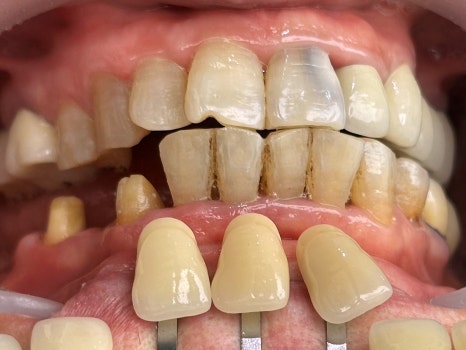

웬만한 치과에서는

'신경치료' 진단을 내렸을 법한

다양한 케이스들도 사실은

(물론 100%는 아니지만)

접착 치의학에 기반한

최소침습 치의학,

<레진 빌드업>으로

당일에 끝낼 수도 있습니다.